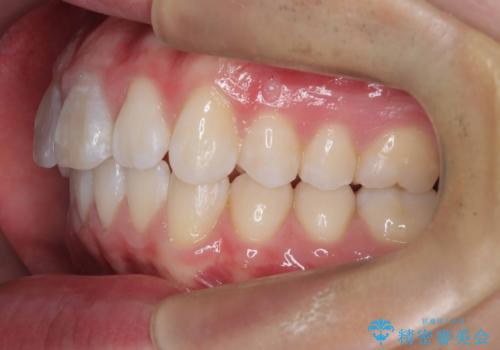

【ワイヤー矯正 11ヵ月で矯正終了!】歯のでこぼこを治したい!

- 「歯のでこぼこを治したい 1年くらいで矯正を終わらせたい」を主訴に来院された患者様です。

叢生量は多く無く歯の傾斜も標準傾斜だったので歯は抜かずにワイヤー矯正で治療を行いました。

左側は2級傾向が強く臼歯の遠心移動をご提案しましたが、1年以内に矯正を終わらせたいという患者様のご意向で希望されず叢生を改善する矯正となりました。